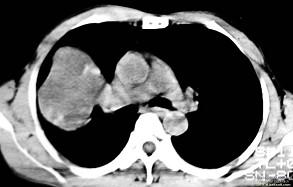

根据所提供的图像,选择最可能的诊断 ( )A.肺内软骨肉瘤B.胸膜间皮瘤C.球形肺炎D.机化性肺炎E.局限性不张

问题 根据所提供的图像,选择最可能的诊断 ( )

选项 A.肺内软骨肉瘤 B.胸膜间皮瘤 C.球形肺炎 D.机化性肺炎 E.局限性不张

答案 A